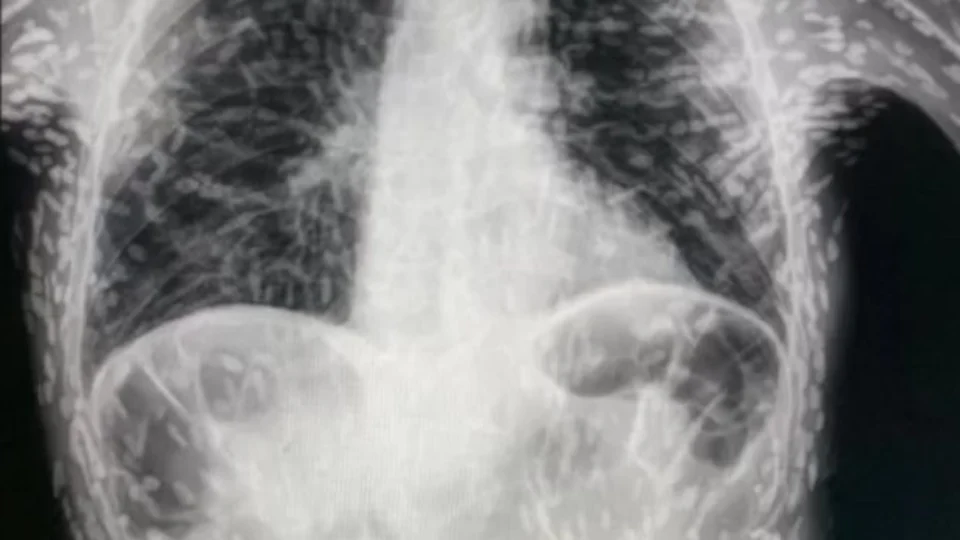

O médico paulista Vitor Borin de Souza viralizou, desde domingo (18), uma postagem no Twitter com exame do tórax de um paciente repleto de ovos de tênia.

Vitor explicou que o quadro envolvia um diagnóstico de cisticercose, com apresentação de tosse constante há dois meses.

Ele ressalta que nas imagens é possível perceber que os ovos de tênia localizados no corpo já estavam mortos, calcificados, e não apresentavam riscos.